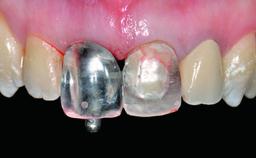

Replacement of an Ankylosed Central Incisor with a Gingival Recession: Tooth Extraction with Socket Grafting and Late Implant Placement with Simultaneous Contour Augmentation

In 2008, a healthy 15-year-old female, non-smoking patient presented at our clinic with a major esthetic problem of tooth 21. Her dental history revealed that the tooth had been avulsed by trauma years before. As a result, the replanted and temporarily splinted tooth had ankylosed and was in severe apical malposition. The ankylosed tooth exhibited a significant gingival recession that disturbed the patient greatly. Due to the patient’s low age and with her skeletal growth not completed, periodic follow-up visits were scheduled to monitor the situation until the patient was old enough for implant therapy.